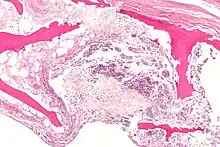

In addition, the Association Research Circulation Osseous (ARCO) suggested a new classification system based on the combination of radiographic, MRI, bone scan and histologic findings. However, apparently these two classifications systems, Ficat and ARCO are still not enough reliable to assess the status of ONFH alone.[2]